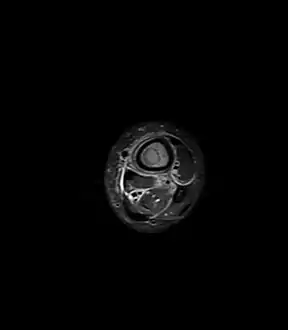

Axial T1-weighted MRI pre-contrast enhancement showing that the intramedullary collection is T1-hyperintense suggesting proteinaceous viscous fluid consistent with infection.